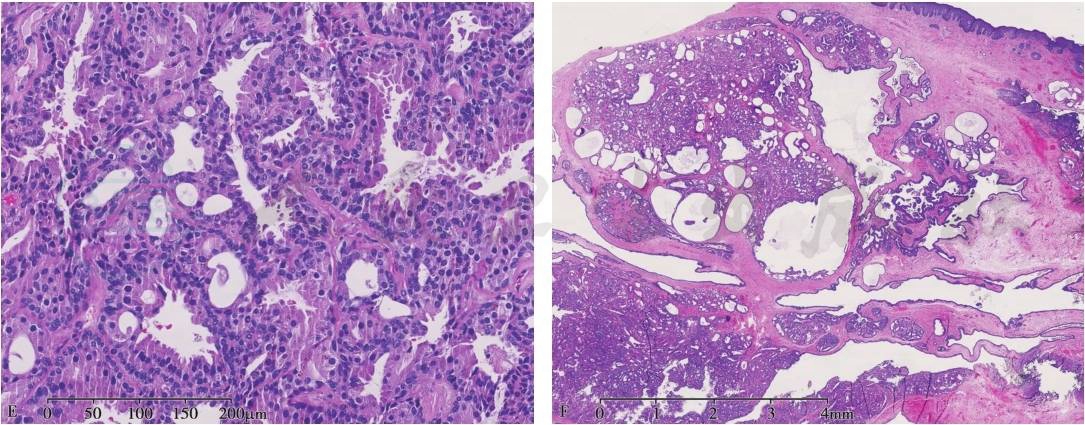

2. 镜下观:肿瘤界限清楚,但无包膜。肿瘤细胞呈腺样或腺管状结构,可有囊性扩张,可伴腔内突起和乳头状增生(图1)。有少量纤维性间质。形态上近似耵聍腺,但缺乏正常耵聍腺的小叶结构。

腺上皮由两层细胞构成,内层细胞可见顶浆分泌,耐酸的荧光黄蜡样色素,胞质丰富、呈酸性,核圆,染色质致密。外层肌上皮细胞可增生,但并不是肿瘤所有部分都明显存在肌上皮细胞。

图1耵聍腺腺瘤

A.肿瘤边界清楚,部分区可见薄层包膜;B.可见不规则脉管及囊状、乳头状结构,底部边缘尚规整;C、D.双层细胞结构,腺腔内可见顶浆分泌;E.双层细胞结构,细胞嗜酸性变,内层细胞伴顶浆分泌;F.肿瘤未见包膜,其内部分区可见大小不等的囊腔形成;G.IHC示CK7腔面细胞强阳性;H.IHC示P63肌上皮细胞核强阳性